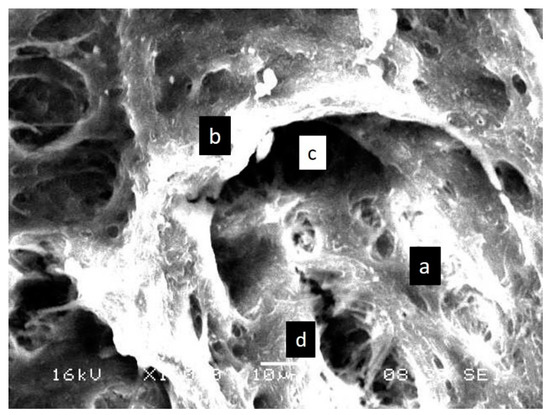

3.1. SEM Analysis